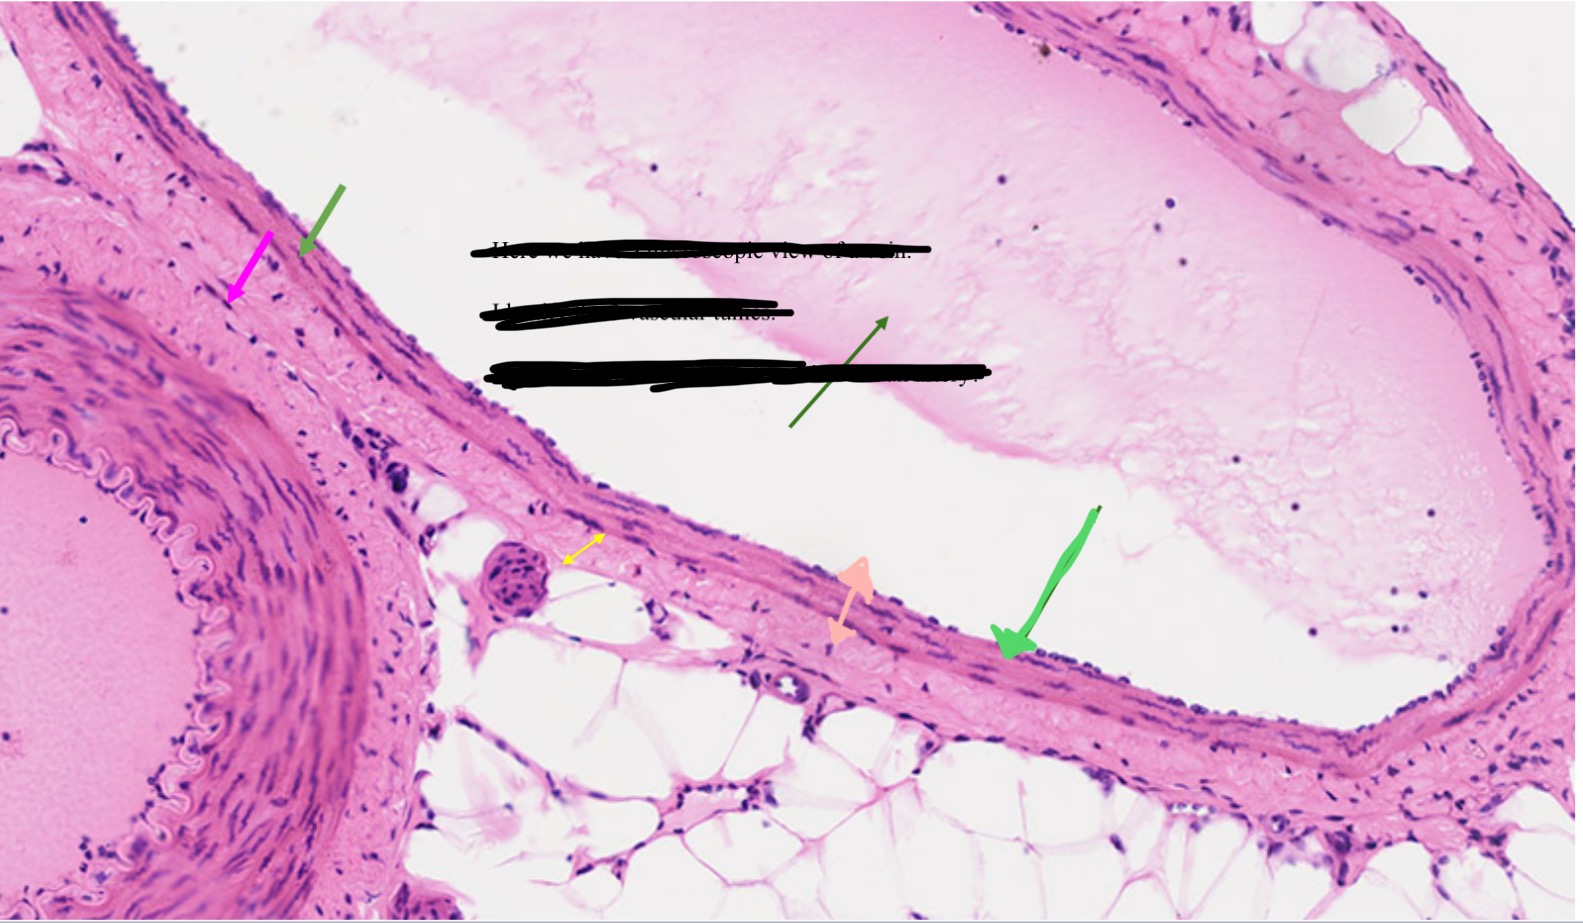

Tunica intima

Name the blue arrow

Lines lumen and release vasoactive chemicals

Function of tunica intima

Venous valves

Name the pink arrow

Prevent backflow of blood

Function of venous valves

Tunica media

Name green arrow

Vasoconstriction and vasodilation

Function of tunica media

Tunica externa

Name the purple arrow

Anchor and bind vessel

Function of tunica externa

Artery

Artery or vein?

Vein

Artery or vein?

Tunica intima

Name the green arrow

Tunica media

Name the yellow

Tunica externa

Name the black

Tunica interna

Name the green

Tunica media

Name the pink

Tunica externa

Name the yellow